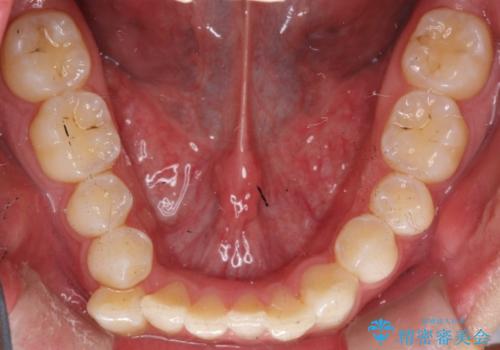

前歯がガタガタ インビザラインによる矯正

- 前歯がガタガタ、下の犬歯が飛び出ているのを主訴に来院されました。

下の奥歯を後方へ移動させてスペースを確保して、前歯を並べる計画としました。

目立たない装置をご希望されたので、インビザラインにて矯正治療を行いました。

使用時間を守っていただけたので、比較的スムーズに矯正を終了することができました。